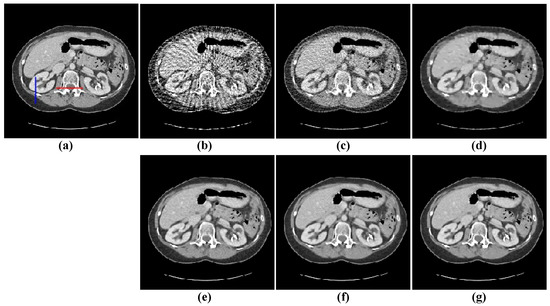

The second image reconstruction experiment is conducted on an abdomen image with more image details to show the feasibility of our algorithm for SVCT reconstruction, as shown in Figure 9. We extracted 80, 64, and 48 views from a full scan and set the parameters as follows: a = 0.5, γ1 = 0.1, and γ2 = 0.06. The reconstructed results using different algorithms are shown in Figure 10, Figure 11 and Figure 12. As can be seen from the figures, our algorithm performs better than other algorithms in preserving small structures and reducing noise. Specifically, FBP reconstruction results contain severe artifacts as displayed in Figure 10b, Figure 11b and Figure 12b. OS-SART reconstruction results also have obvious noise as displayed in Figure 10c, Figure 11c and Figure 12c. TV has a better performance than FBP and OS-SART, but the result has blocky artifacts, as displayed in Figure 10d, Figure 11d and Figure 12d. The PICCS and TVPI-G algorithms have an improvement in image quality, but fine image structures are losing detail and some edge information is blurring, as displayed in Figure 10e,f, Figure 11e,f and Figure 12e,f. As can be observed from Figure 10g, Figure 11g and Figure 12g, the proposed algorithm performs better not only in preserving edge and image details, but also in reducing noise.

Subsequently, we select two ROIs, marked by a red box as shown in Figure 10a and Figure 11a, and zoom in on them to show the results. The enlarged ROIs are shown in Figure 13. It could be observed that our algorithm can reconstruct some of the important tissues shown by the arrows, which are blurred or difficult to see in other ROIs. To show the accuracy of the different methods for local reconstruction of CT images, we plot the 1D line intensity distribution in CT images reconstructed from 80 projections in two regions (shown as blue and red lines in Figure 12a); the curves are as shown in Figure 14. Visually, it can be seen that the line intensity distribution of the image reconstructed by the proposed method is the closest to the original CT image in these two regions. In comparison, the proposed reconstruction algorithm in this paper is more accurate. At the same time, the red enlarged part of the figure indicates the edge area, from which it can be seen that the proposed algorithm has better performance in edge protection.

Figure 10. 48-views reconstruction results of abdomen image: (a) ground truth, (b) FBP, (c) OS-SART, (d) TV, (e) PICCS, (f) TVPI-G, and (g) NPICCS. The display window is [−150 250] HU.